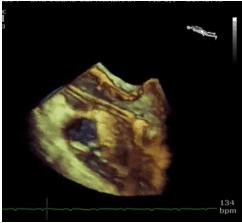

Identifique o nome do dispositivo protético presente na foto abaixo.